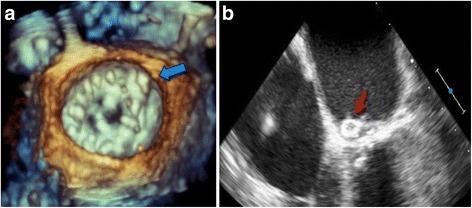

We present a case that displays the unique therapeutic challenges of treating a patient who developed both LVOT obstruction and mitral PVL after undergoing surgical aortic and mitral valve replacement (MVR). We also describe the use of alcohol septal ablation and albumin-glutaraldehyde (BioGlue) for septal ablation to percutaneously treat the patient's LVOT obstruction, followed by use of an Amplatzer vascular plug for percutaneous closure of an antero-medial mitral PVL associated with severe regurgitation.